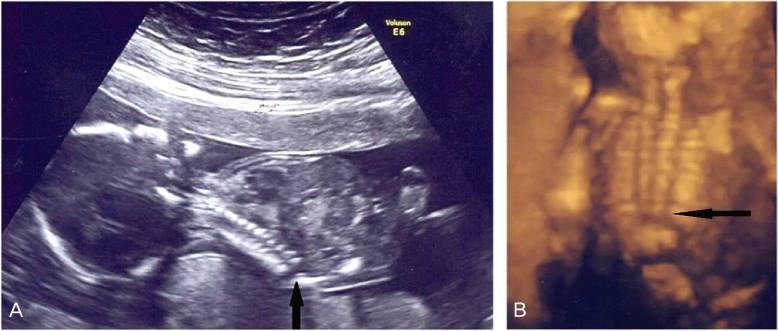

What is Camptomelic Dysplasia?

Camptomelic Dysplasia: bowing of the long bones

What are the most common bones affected by Camptomelic Dysplasia?

tibia

femur

What is the sonographic appearance of Camptomelic Dysplasia?

bowing of long bones

hydrocephalus

hydronephrosis

What are the anomolies associated with Camptomelic Dysplasia?

heart disease

hydrocephalus

hydronephrosis

What is caudal regression syndrome caused by?

early disruption of caudal portion of the neural tube

(sacral anomolies)

includes a range of anomolies

What is caudal regression syndrome?

fusion of the lower extremities

male prevalence 3:1

What is a mild case of caudal regression syndrome?

sacral anomalies

What is the most severe form of caudal regression syndrome?

Sirenomelia

Caudal regression syndrome

What are the associated anomalies of caudal regression syndrome?

diabetes

monozygotic twins